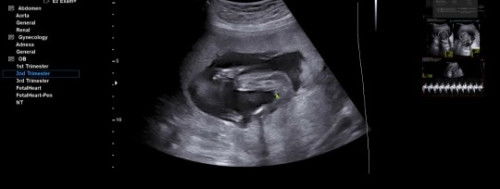

Jk baby cewe/cowo

Bun, kira kira ini cewe/cowo yah dokternya masih ragu, katanya cewe. #Sharing_dong_Bund

kayanya itu mah kaya aku. cowo. rada keliatan monas nya

cewek bun. sy persis gt kmren pas usg

ini pas 18week